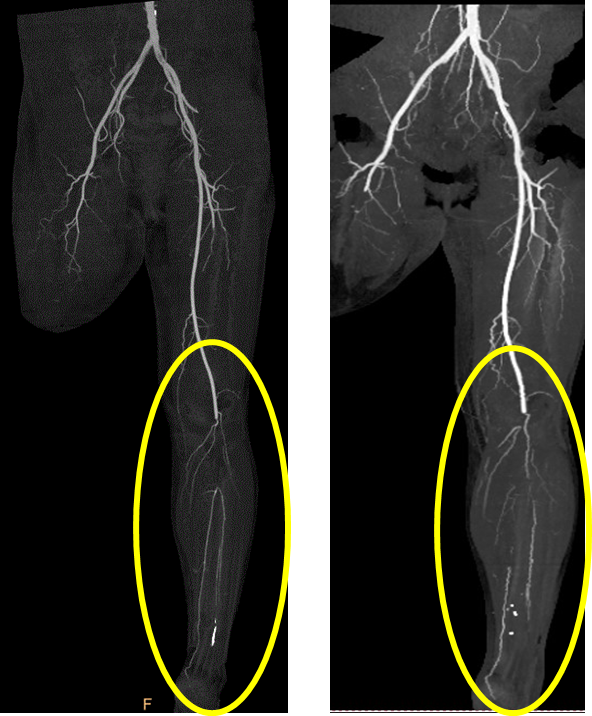

术前 术后

治疗第四天,血供改善,胫后动脉搏动恢复,缺血症状明显改善

2021.8.8 2021.8.20